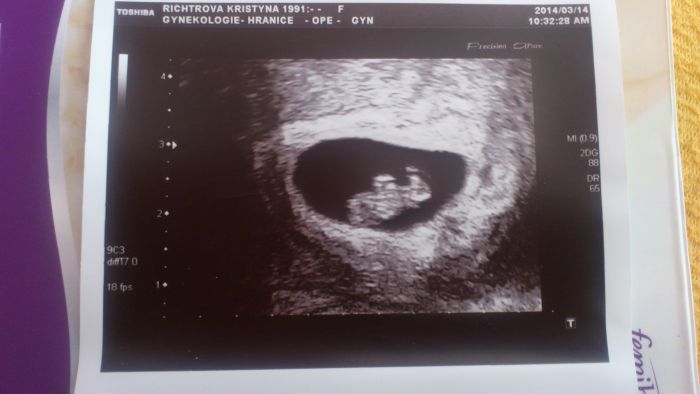

[483892]

Tynuš,krásná fotečka který jsi týden?

Autor: Tynus.kaaa 14.3.2014 v 14:01

[483893] Podle doktora 7+5